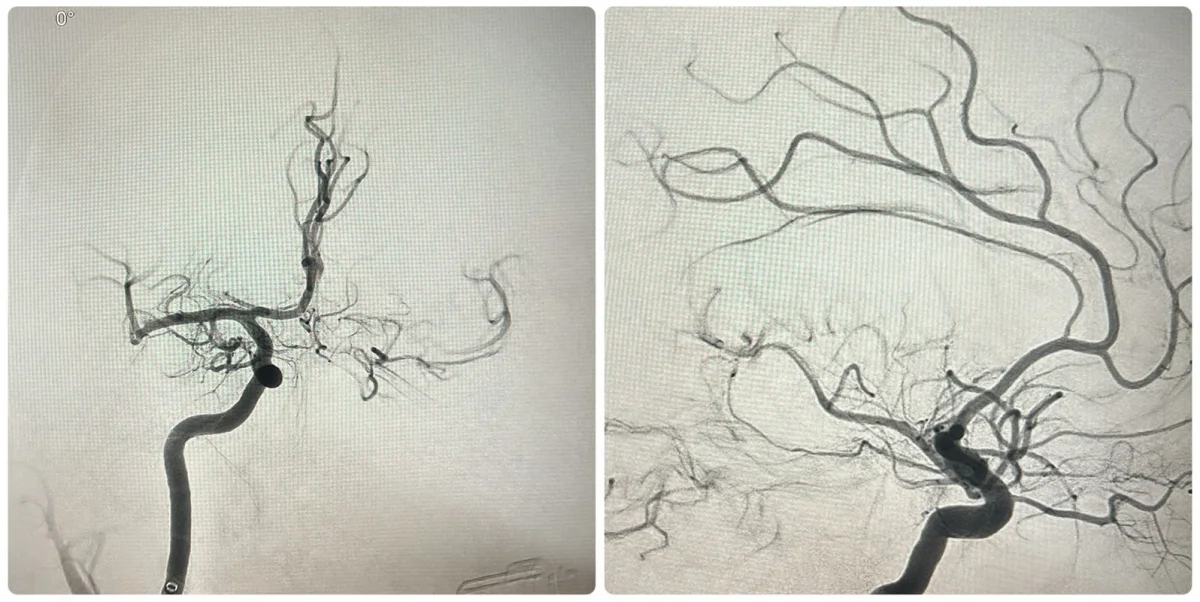

Пациенту оперативно провели компьютерную томографию. Несмотря на то, что явных признаков кровоизлияния или сформированного очага ишемии выявлено не было, данные КТ были дополнительно обработаны специализированной программой искусственного интеллекта RAPID. Эта система позволяет оценить ранние признаки инсульта и определить целесообразность проведения операции по удалению тромба.

Врач отметил, что при ишемическом инсульте решающее значение имеет время: чем раньше выполнено вмешательство, тем меньше повреждаются клетки головного мозга и выше шансы на полное восстановление. Используемая программа RAPID оценивает мозг по шкале ASPECTS (от 0 до 10 баллов) и помогает определить степень поражения в бассейне средней мозговой артерии.